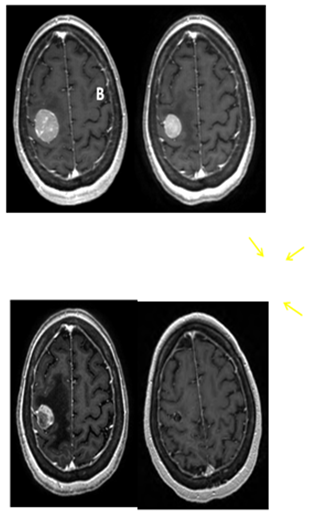

The patient returned for simulation in preparation for frameless SRS on August 17, 2012, 12days after her initial brain MRI. CT simulation was performed using 2.4mm slice thickness. The Brain LAB Novalis Radio surgery System (iPlan RT V4.1, BrainLAB, Heimstetten, Germany) was used for the treatment planning and delivery. The original (pre-steroid) MRI from August 5, 2012 was registered and fused to the CT images for target delineation. The gross tumor volume (GTV) was contoured based on the isotropic 1mm thickness 3D MRI using a gadolinium enhanced T1 sequence (Figure 2A). However, when the GTV was superimposed on the CT images, it became clear that there was a significant mismatch. The hyperdense metastatic lesion was quite easily seen on the simulation CT images, even without IV contrast (Figure 2B). This prompted the decision to abort SRS. A repeat MRI was obtained on August 21, 2012 using identical imaging parameters. The new MRI showed stable enhancing right posterior cortical mass, but with improved surrounding vasogenic edema (Figure 1C) (Figure 1D). A second treatment plan was constructed based on the new MRI. The patient underwent SRS treatment on August 22, 2012. The final planning target volume (PTV) was 11.69cm3. Because of the relatively large volume (>10cm3) and eloquent location of the tumor, it was decided to prescribe 16Gy to the 90% isodose volume. Prior to dose delivery, target-localization was performed using the Brain LAB image-guided positioning system (ExacTrac V5.5.2). The treatment was delivered via 6 non-coplanar dynamic arcs, without difficulties. The patient tolerated SRS well.

Figure 2 The tumor was contoured (green line) on pre-steroid MRI (A) and superimposed on CT simulation images (B). The tumor was identified as a well-defined, hyperdense mass on planning CT, even without IV contrast. Interval tumor migration has clearly occurred during 12 days between the acquisitions of these two scans.

SRS is image-based treatment. All salient anatomic features of the SRS patient, both normal and abnormal, are commonly defined with CT and/or MRI. Both high three dimensional spatial accuracy and tissue-contrast definition are critical to the optimal definition of target(s) and critical structures for SRS. Imaging, whether CT or MRI, is crucial for localizing target boundaries as well as generating target coordinates for accurate treatment beam localization. Precise SRS treatment planning and delivery requires as a prerequisite that the target position is unchanged between image acquisition and treatment planning and delivery. In general, an intracranial target is not considered a moving target. Therefore, with rigid image registration and fusion, the MRI defined target and normal structures should accurately represent their relative physical position in space. Re-imaging of the brain is often done to evaluate for possible tumor progression, however, target migration between the time of imaging and treatment planning and delivery is typically not a concern. The present case illustrates a potential pitfall in the commonly made assumption that the location of the intra-cranial target is fixed in relation to the cranium and surrounding structures. In this study, the tumor position shifted within 12days, as shown in Figures 2 & 4. This resulted in a significant GTV mismatch of 3.312cc (28.3%) and a shift of the isocenter by 3.4 mm posteriorly, 0.3mm laterally and 2.5mm inferiorly (Figure 4). As demonstrated in Figure 5, if the pre-steroid MRI had been used for target delineation and planning, a significant portion of the GTV would not have been covered by the prescription dose (90% isodose line). The DVH confirmed that only 83% of GTV would have received the prescribed dose (Figure 6). Conversely, this could also have led to a significant overdose to the normal brain, in this case, the post central gyrus (Figure 2B) (Figure 2C). Quantitatively, 0.47cm3 more normal brain would have received the prescription dose of 16Gy, an increase of 17% compared to the treatment plan that the patient had actually received (3.24cm3 vs. 2.77cm3, respectively). Evidently, dexamethasone significantly decreased the peritumoral vasogenic edema, allowing the tumor to shift anteriorly and decompressing the post-central gyrus. If undetected, this would have represented the worst scenario for SRS, manifesting both inadequate tumor coverage, and extremely high normal tissue dose.